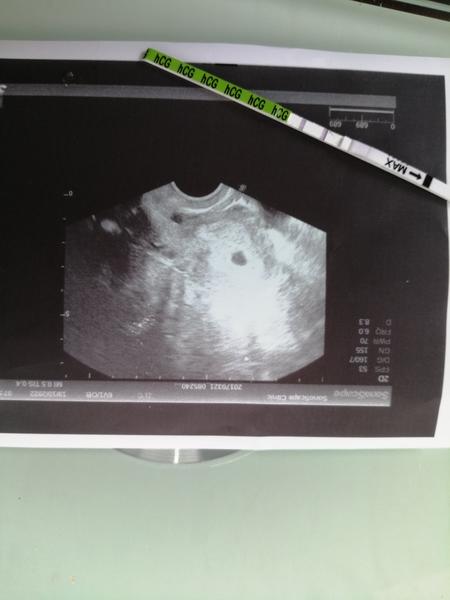

Prvni fotka 7+1 a druha 9+4 😊😊